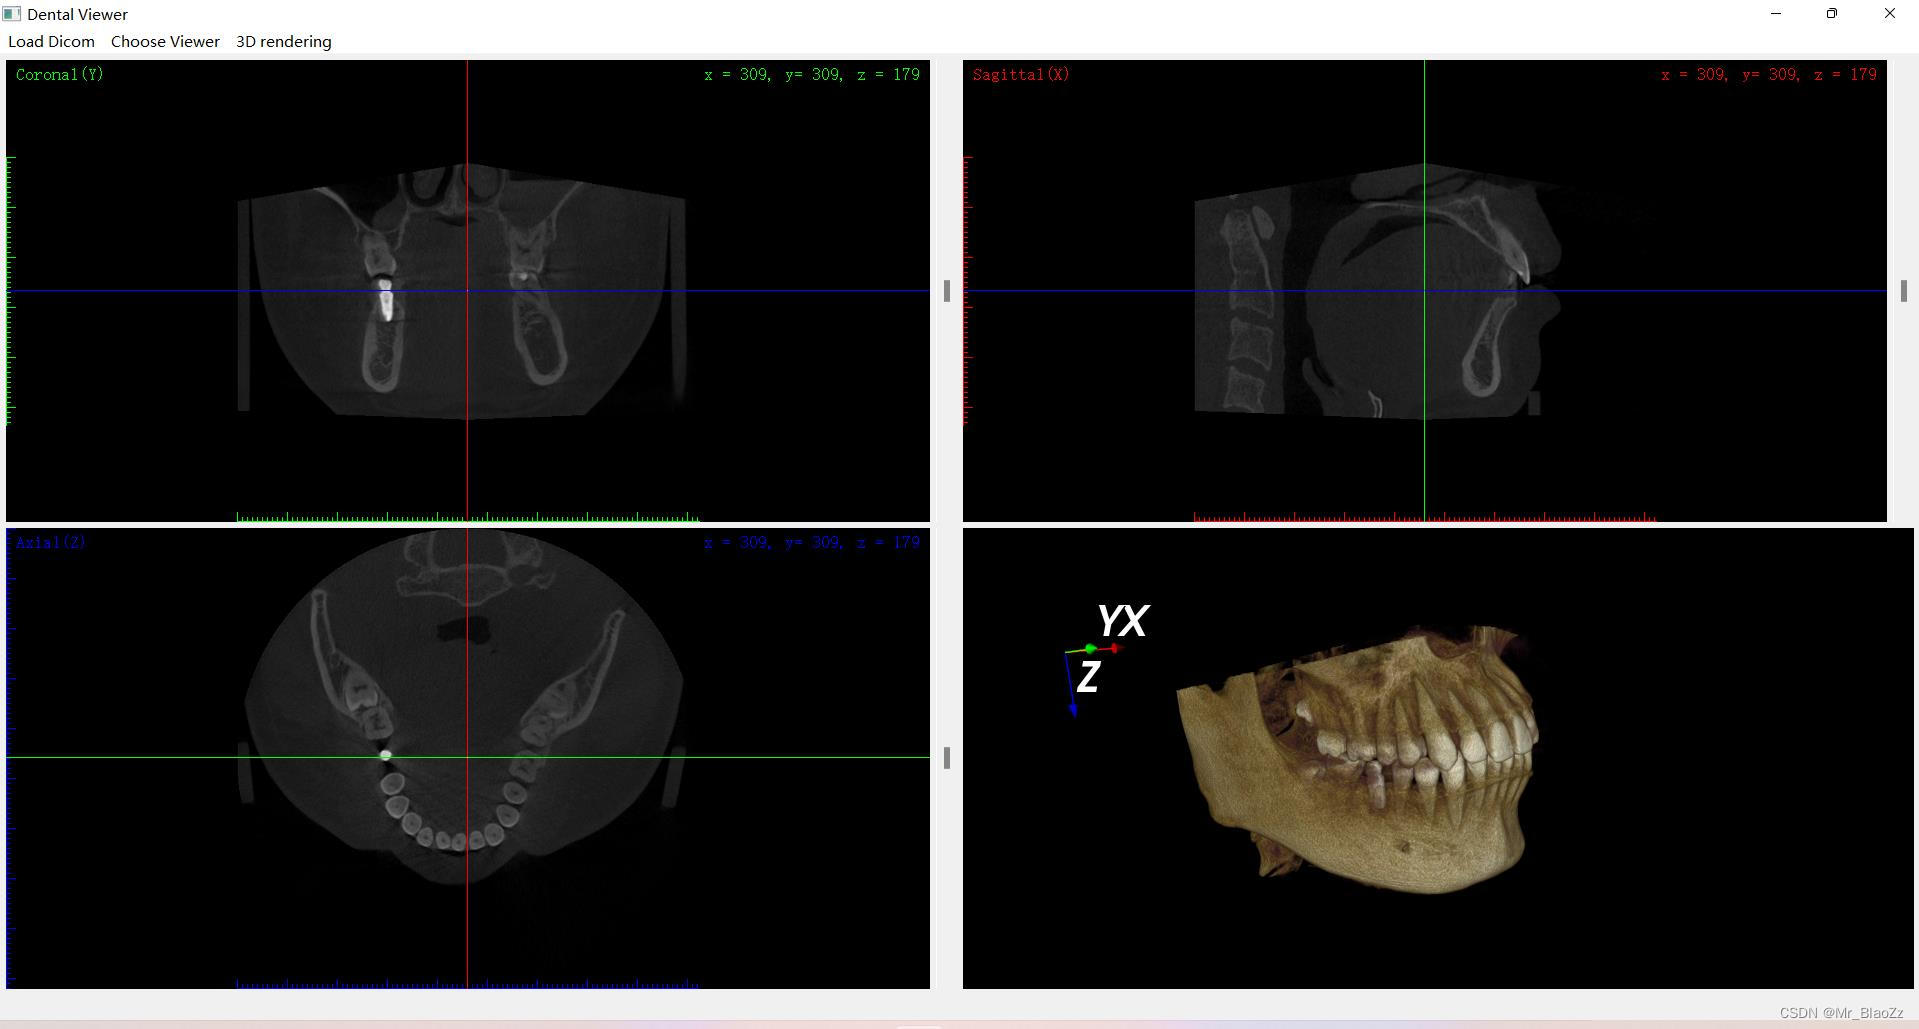

这次仿照一个软件的布局,实现了这款软件的大部分功能,功能大致差不多,主要使得整个界面布局以及内容更加完善,主要包含三个界面:三维视图、全景视图、种植视图。同时,也稍微了解下vtk库,实现了三维重建,基本了解了vtk的坐标系原理、坐标值、vtk空间中的各种绘制等等,但这些代码还没有完全整理出来。测试了三维模型的实时更新占用内存较多。后续会逐渐向vtk三维空间和界面交互方面完善。

ps:对于之前有些人一直问关于这个界面的部分,其实把CT数据当成一个长方体,用三把刀从上下、前后、左右三个方向去切这个长方体,然后三个面交于长方体内一点,就可以很好理解MPR图像了。另外,这里所有一个界面内所有视图都是联动的!由于本人未还未毕业暂不公布源码,有兴趣的可以评论交流就行。

仿造软件布局实现大部分功能,包括三维、全景和种植视图。初步掌握vtk库进行三维重建,理解坐标系原理。注意到三维模型实时更新内存消耗大,计划改进交互与界面。CT数据解释MPR图像原理,所有视图联动,未公开源码,欢迎交流。

仿造软件布局实现大部分功能,包括三维、全景和种植视图。初步掌握vtk库进行三维重建,理解坐标系原理。注意到三维模型实时更新内存消耗大,计划改进交互与界面。CT数据解释MPR图像原理,所有视图联动,未公开源码,欢迎交流。